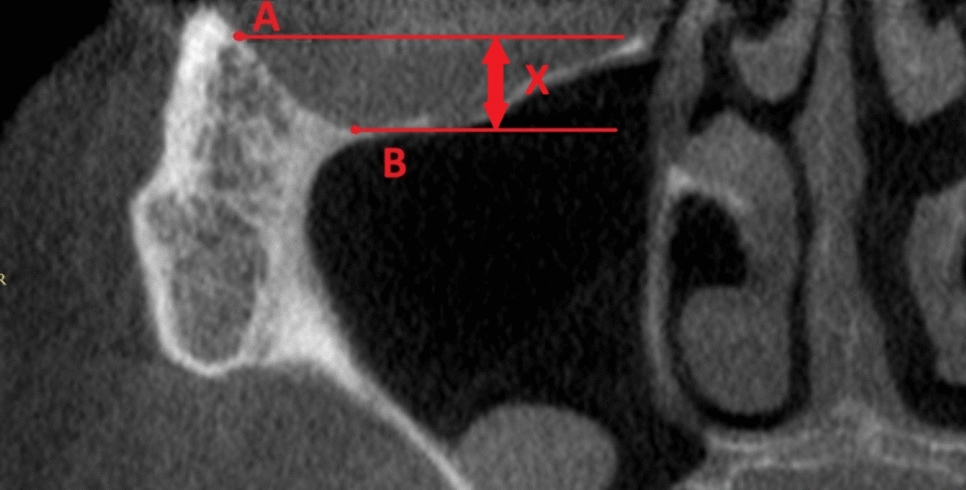

Zygomatic Orbital Floor (ZOF)

Anatomy was thoroughly investigated by measuring the undercut of the lower and lateral walls of the orbit. Reference points in the frontal plane on the CBCT were the lowest point on the lower wall (B) and most lateral point (A) in the lateral wall of the orbit.

Two simple lines, parallel to each other and parallel to the horizontal plane, were prolonged, and the distance between them [x] was the authors’ own invention, the zygomatic orbital floor (ZOF) (Fig. 3).

Fig. 3

Reference points in the frontal plane on cone-beam computed tomography (CBCT) were the lowest (B) and the most lateral point (A) in the lower wall of the orbit

The ZOF was divided into four classes:

Class I: 0–3 mm—flat.

Class II: 4–6 mm—moderate.

Class III: 7–9 mm—deep.

Class IV: more than 10 mm—extremely deep.

Simple regression and box and whisker plots were used to assess if ZOF classification was age-dependent. Analysis of variance (ANOVA) assessed if statistical significance existed between ZOF classification and anatomical structures—width on both sides and height of the ZB. The ZOF classification determines the angle of the zygomatic implants. The higher the ZOF classification, the lower the zygomatic implant must be situated in the zygomatic bone.

The ZOF classification was used before the surgery for surgical planning and the placement of zygomatic implants. By paying attention to the ZOF class, the operator avoided performing an osteotomy in the orbit. The measurements were utilized to plan not only the distance from the orbital rim to the osteotomy, which was marked with a pencil before drilling, but also to assist in planning the entire treatment, including the number of zygomatic implants on one side.

The ZOF classification has a significant impact on evaluating postoperative treatment because it not only makes the procedure safer but also helps determine the number of zygomatic implants, thus influencing the force distribution in the prosthodontic bridge.